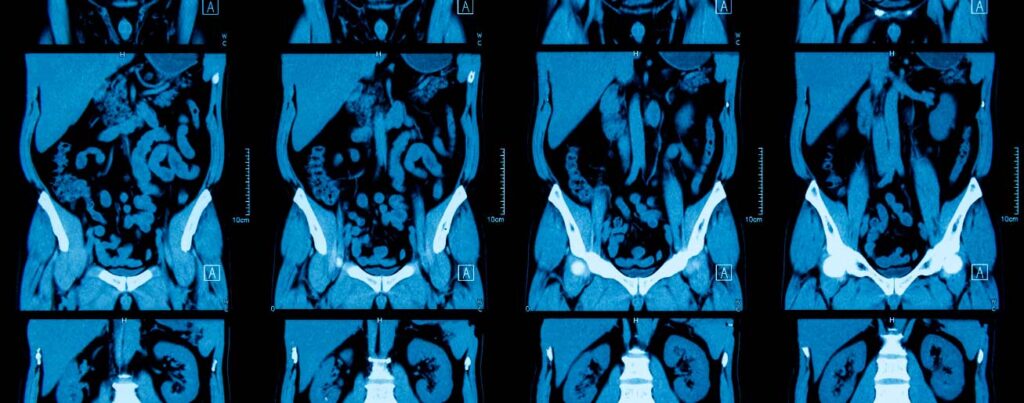

Você sabia que o exame de Tomografia do Abdômen é fundamental para a sua saúde como um todo? Entenda melhor sobre sua importância